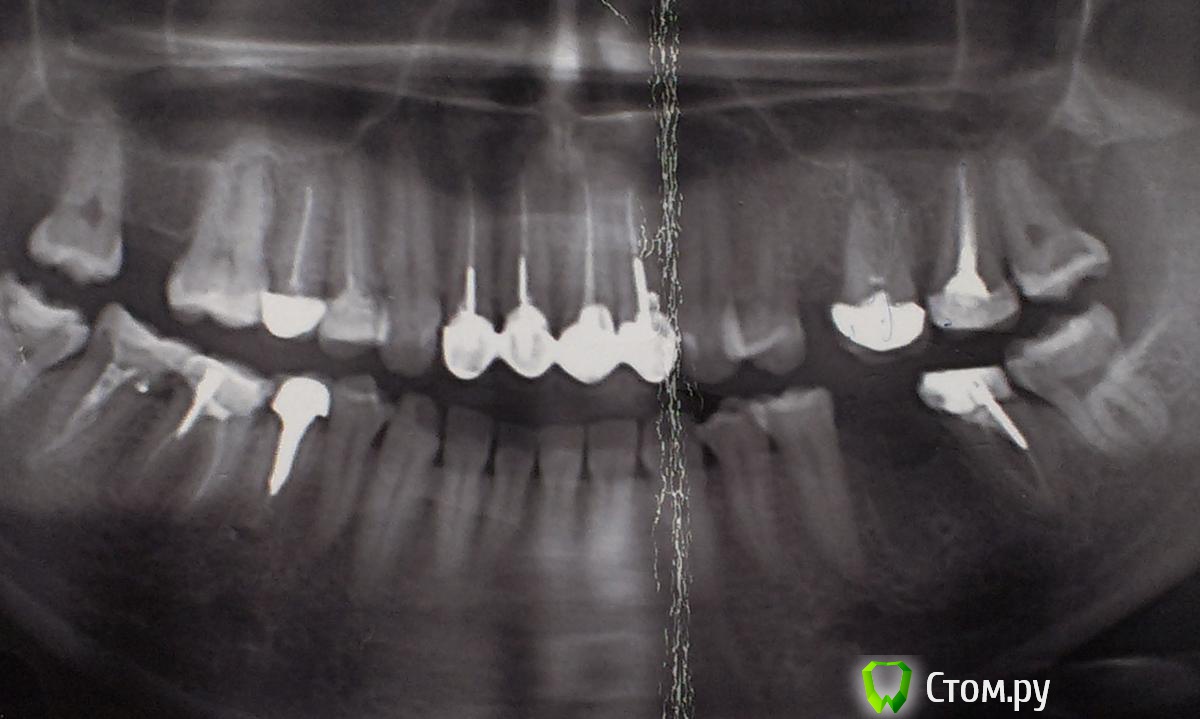

Ольга97-99 Опубликовано 6 сентября, 2014 Поделиться Опубликовано 6 сентября, 2014 Добрый день, уважаемые стоматологи. Прошу помощи... Ситуация с зубами плачевная... Не буду долго расписывать о том, как с 10 лет я не вылезаю из кресла стоматолога. Леченые зубки в небольном городе Н. Постоянно выпадающие пломбы, приводящие к повторному лечению. Депульпированны практически все. Периодичность посещения стоматолога - 3 мес., + манипуляции парадонтолога. Но к 26 годам имеем нижепредставленное.. С задними зубами все более или менее ясно - еще несколько на удаление, затем имплантация. С передними верхними... МК коронкам 7лет. Не беспокоят, боли, дискомфорта нет. Но эстетика оставляет желать лучшего. Еще, как говориться, не везет так не везет - улыбка десневая. И поднявшаяся синюшная десна во всю сияет. Было решено - настало время перемен. Мой обход ортопедов в нашем славном городе начался с мыслью вдохновляющей "заменить мк на дц". Более натуральный вид, к тому же рецессия десны должна была остановиться, так Интернет и доктора говорили )). Что имеем сейчас, мнения двух (на мой взгляд самых адекватных спецов) ортопедов: Первый: снимаем коронки, смотрим состояние корней. Если все нормально, штифты не трогаем, меняем пломбы и делаем дц. Но 80-90% вероятность, что корни испортились, либо будут повреждены (при снятии коронки выйдет штифт, разрушив корень). Тогда удаление, затем имплантация. Не буду портить мнение о себе и писать, что я испытывала после такого вердикта.... Второй: (его, кстати, посоветовал 1й) глянул (бегло) на мой снимки, говорит: снимаем коронки, вынимаем штифт, лечим каналы, делаем вкладки из дц, делаем коронки из дц. На мой вопрос "а если корень поврежден? или еще что-то не так пойдет" был ответ "зачем тебе это все знать, я доктор и я говорю тебе - будут коронки нормальные". Думаю, не стоит уточнять, что гарантий по сроку службы новых коронок я не услышала. Ну верней, прозвучала классика про кирпич на голову. Понятно, какой вариант мне запал в душу, и чего я бы хотела.. Но я могу хотеть одного, а реальность может быть совсем другой.. Не имею право на неоправданный риск, это же передние зубы... Пожалуйста, посмотрите снимки. Можно услышать Ваше мнение насчет возможности замены протезов передних верхних зубов. Заранее спасибо!!! Ссылка на комментарий

Korel Опубликовано 8 сентября, 2014 Поделиться Опубликовано 8 сентября, 2014 Вопрос о состоянии корней остается открытым до момента снятия коронок, я правильно понимаю? Нет, не правильно. Ваши корни видны на R-снимке. Открытым остаётся вопрос о состоянии культей скрытых коронками. 1 Ссылка на комментарий